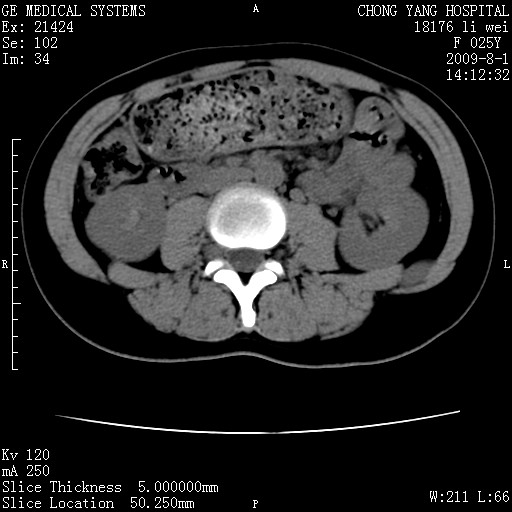

以下是引用pujunzhi在2009-8-1 20:23:00的发言:[br]胸椎旁及背部肌间良性病变,范围广,边界清,沿肌间生长,考虑淋巴管瘤、血管瘤,建议增强扫描。

以下是引用拾荒者在2009-12-30 21:45:00的发言:[br]ct21383:神经纤维瘤病( nf) [br] [br] 神经纤维瘤病。四肢都有,影响美观,四肢上的手术了。[br] [br] [br]谢谢!